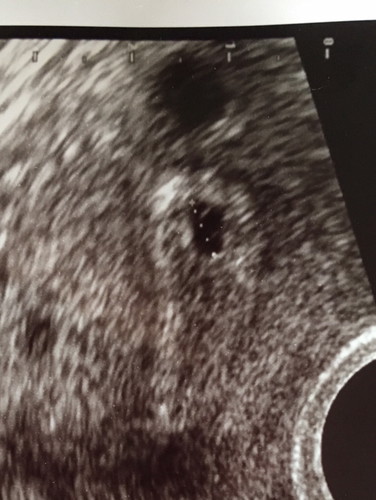

5w 3 d

ผลอัตราซาวด์เมื่อวาน หมอบอกมีรอยเลือดในมดลูกเลี่ยงต่อการแท้งมากๆให้ยากันแท้งมาทาน ตอนนี้กังวลใจมากๆค่ะ